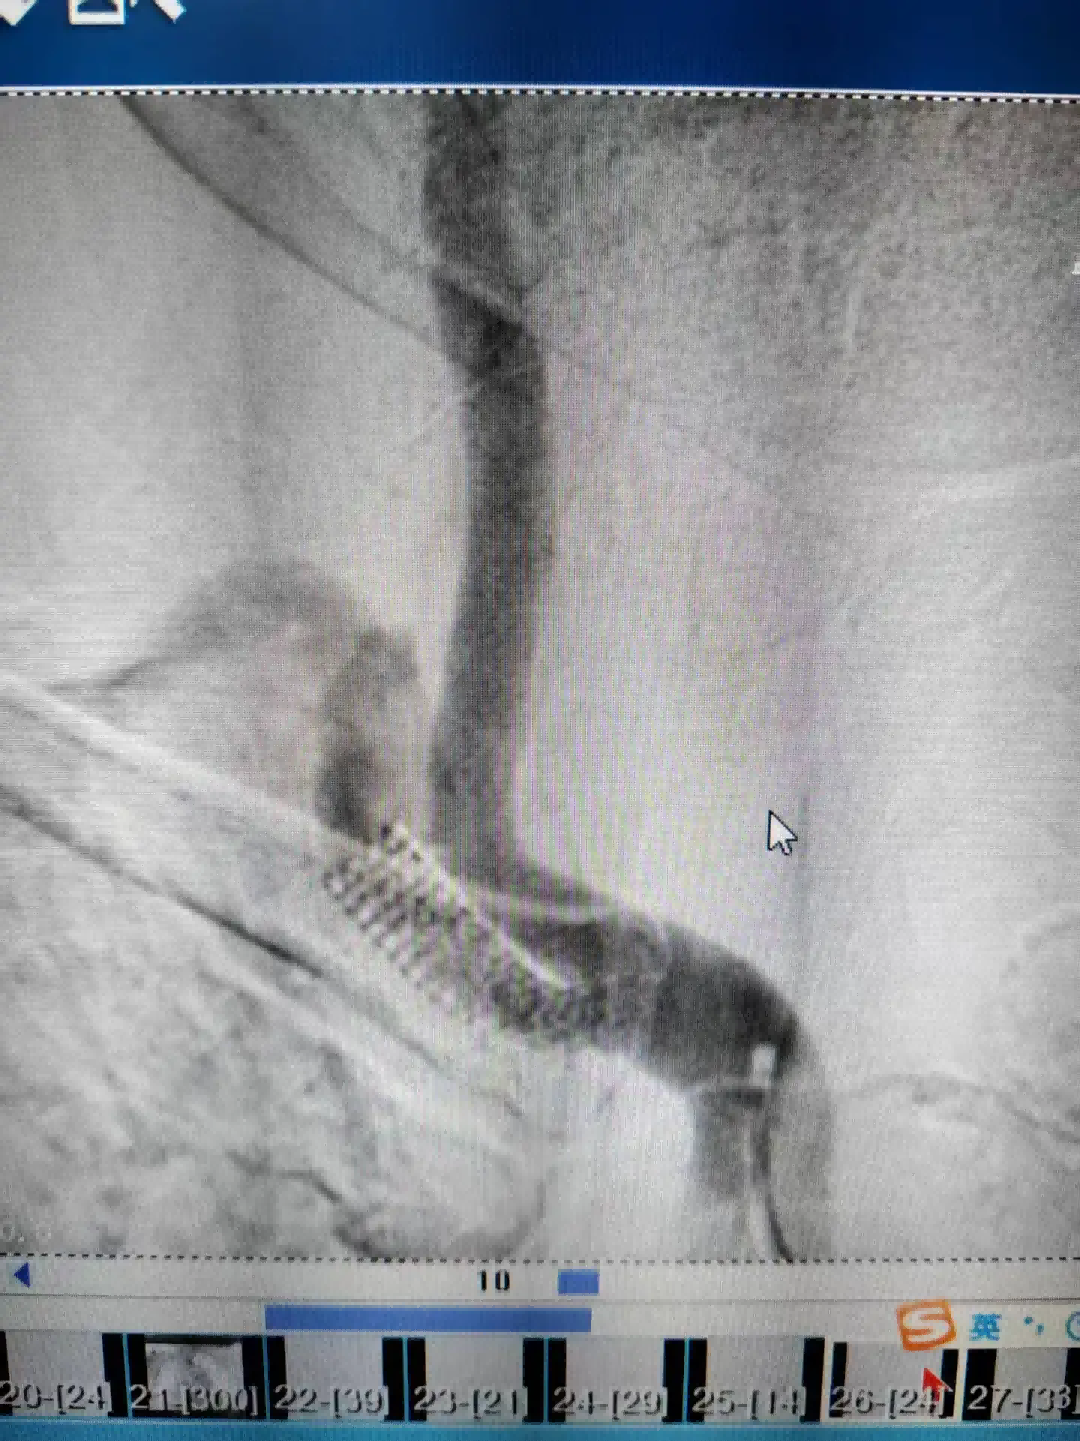

为进一步明确病情,12月23日,医生为王阿姨进行了脑血管造影检查。结果提示,其右侧锁骨下动脉狭窄程度较两年前明显加重,手术指征明确。经与家属充分沟通并取得同意后,神经内科团队随即为王阿姨施行了右侧锁骨下动脉支架植入术。手术顺利,术后造影显示血管狭窄段已被成功扩开,血流恢复通畅。

术前与术后对比术后,王阿姨的头晕症状得到显著改善,生活质量大幅提升。出院前,她特意将一面锦旗送至神经内科:“谢谢你们帮我解决了这么多年头晕的老毛病,现在整个人都轻松了!”。